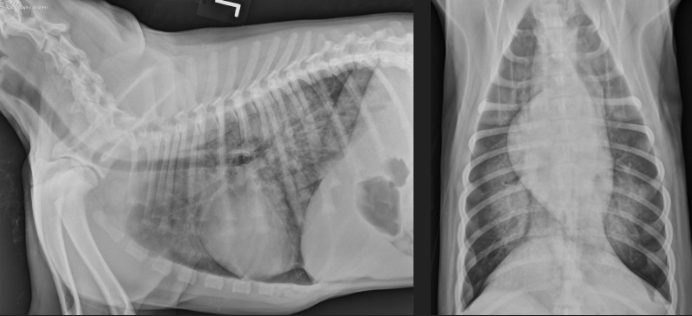

Atelectasis

note the mediastinal/cardiac shift to the right and the soft tissue opacity of right middle lung lobe

What condition?

Atelectasis secondary to pneumothorax

note: retraction of lung lobes from thoracic wall and soft tissue opacity of left and right middle lung lobe